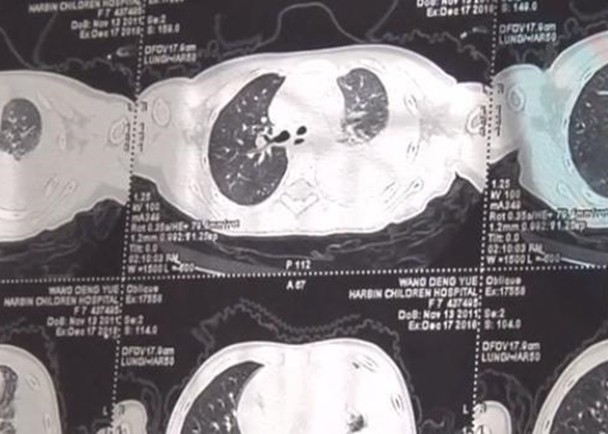

Phổi của bé Nguyệt bị viêm nặng.